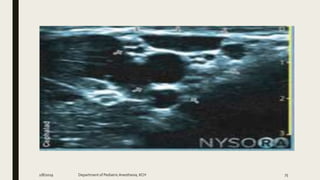

QL BLOCK

2/8/2019 Department of PediatricAnesthesia, KCH 97